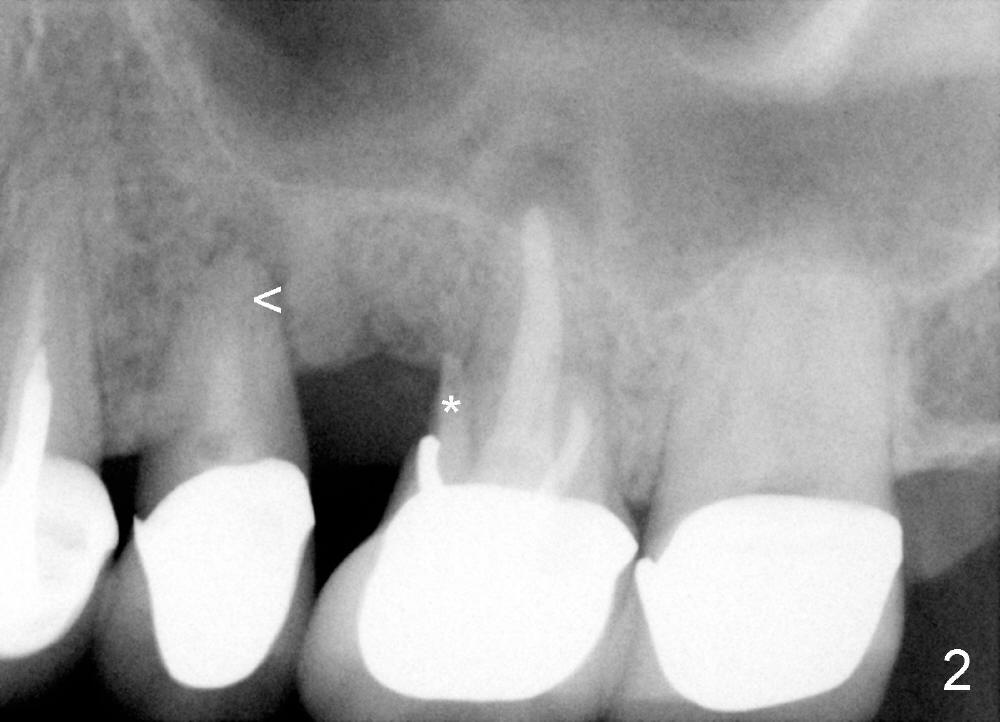

吴先生从小牙齿不好,挺能理解人,所以我们关系还能维持七八年。第一次他来时,我们诊所刚开张,没有多少病人,他左上第一磨牙近中根纵裂(图一:14**),花时间做根切(root amputation,切除近中根近中游离部分),其余两个根做根管治疗(图二)。不久以后他一直有轻微前臼齿区不适,好像第二前臼齿根管治疗充填不佳(图二<),根尖有阴影,不妨重做根管治疗(图三R),之后问题没有解决,根尖切除后,还是好好坏坏,那么再做一次根管治疗(图四R)。好不容易等到他认为疼痛来自于第一前臼齿:颊侧根充填不到位(图四箭头),鄂侧根好像有个牙桩(其实是银汞拴(Amalgam plug)),好像没有根充。这没有什么了不起:除去牙冠,牙桩,重做根管治疗,我们样样都能做。鄂侧根管很快搞通,但是颊侧根管根尖1-2 mm 阻塞,无可奈何。根充(30/.06 for L, 55 for P)后,插入两个三号Coltene Whaledent stainless steel posts以及做牙冠。每当他回来洗牙,汇报前臼齿区仍有不适,不知那颗牙齿有毛病时,对颊侧根管处理不当深感内疚,问题真得出于那里吗?